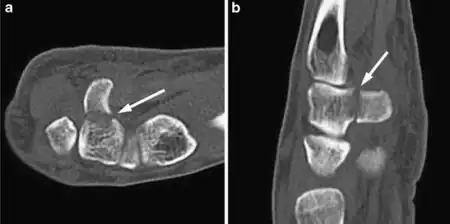

The cause is typically injury during racket sports, baseball, or golf or a fall onto the hand.[1][2] Types include hook (most common) and body (proximal pole, medial tuberosity, sagittal oblique, and dorsal coronal).[1] Diagnosis is typically by X-rays, but may require special views such as a carpal tunnel or supinated oblique view; or a CT scan.[1]

Treatment when the bones of well aligned is generally orthopedic casting for 4 to 6 weeks; though there is a high risk of it not healing.[1] Otherwise surgery is indicated.[1] For hook fractures surgery generally involves removal of the hook.[1] Hamate fractures represent about 2% to 5% of breaks of bones within the wrist.[1][2]